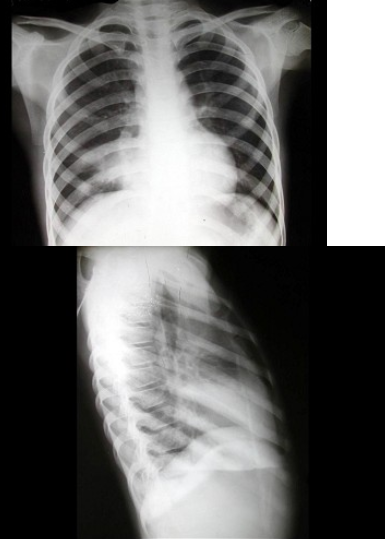

89、单项选择题

男,5岁,发热、咳嗽、气逼,听诊右中肺呼吸音减弱。结合胸片,最可能的诊断是()

A.大叶性肺炎

B.右肺中叶综合征

C.小叶性肺炎

D.原发性肺结核

E.淋巴瘤